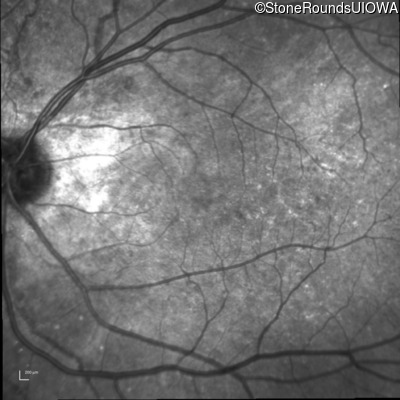

Infrared Fundus Photograph - Right - 20/20 -1

Exemplar